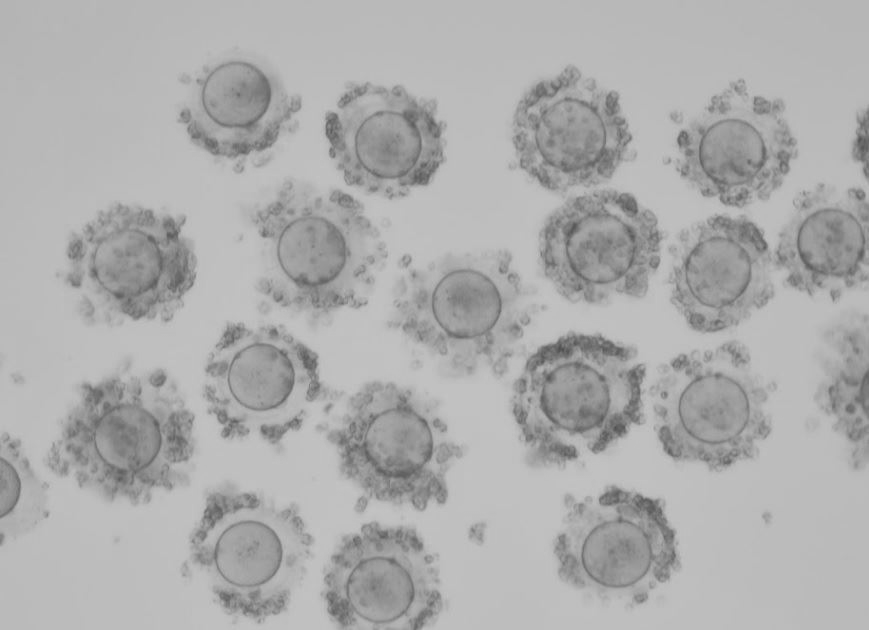

Q: 試管嬰兒治療,是否取到的卵數目越多成功率就越高?

這篇研究蒐集了15000個病人,皆為第一次接受試管嬰兒治療,分析其取卵數和累積活產率的關係。

研究的結論是「取卵數越多,累積活產率越高;當取卵數大於25個以上時,累積活產率可以高達70 %」

這個研究給我們的暗示就是病人第一次做試管嬰兒的時候,倘若能夠取到比較多的卵,就盡量想辦法達到這個目標。也就是告訴我們越年輕、卵巢功能越好時候做,成功的機率會比較高。

但是到底能夠取到幾顆卵,實質上並不是用藥越強取到卵的數量越多,這往往要取決於病人的卵巢功能。